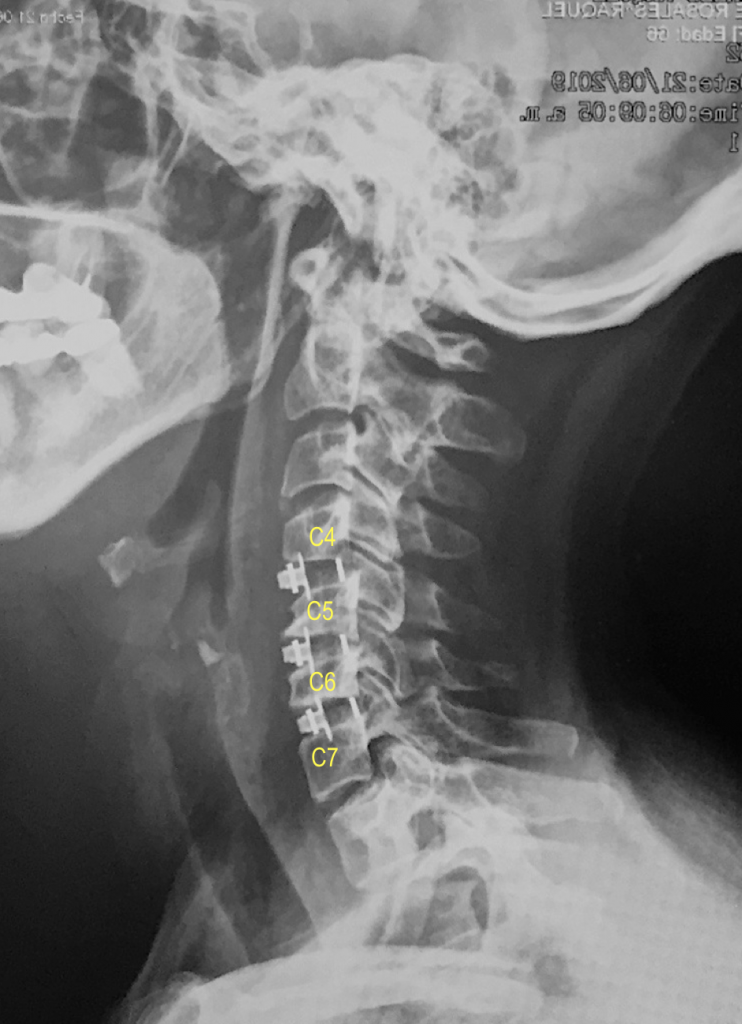

Paciente: RAR

Edad: 67 años

Diagnóstico: Trastorno de Disco Cervical con Radiculopatía C4C5C6C7C6C7

Tipo de Cirugía: Artrodesis Cervical Anterior, mediante acceso tubular, por microcirugía C4C5C6C7.

Fecha de la cirugía: Junio 19 del 2019